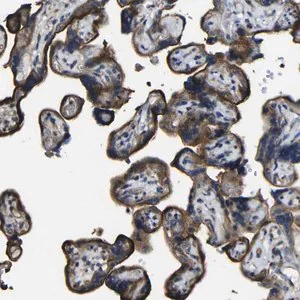

Anti-NAALADL2 antibody produced in rabbit

Prestige Antibodies® Powered by Atlas Antibodies, affinity isolated antibody, buffered aqueous glycerol solution

immunofluorescence: 0.25-2 μg/mL

immunohistochemistry: 1:50-1:200

western blot: 0.04-0.4 μg/mL